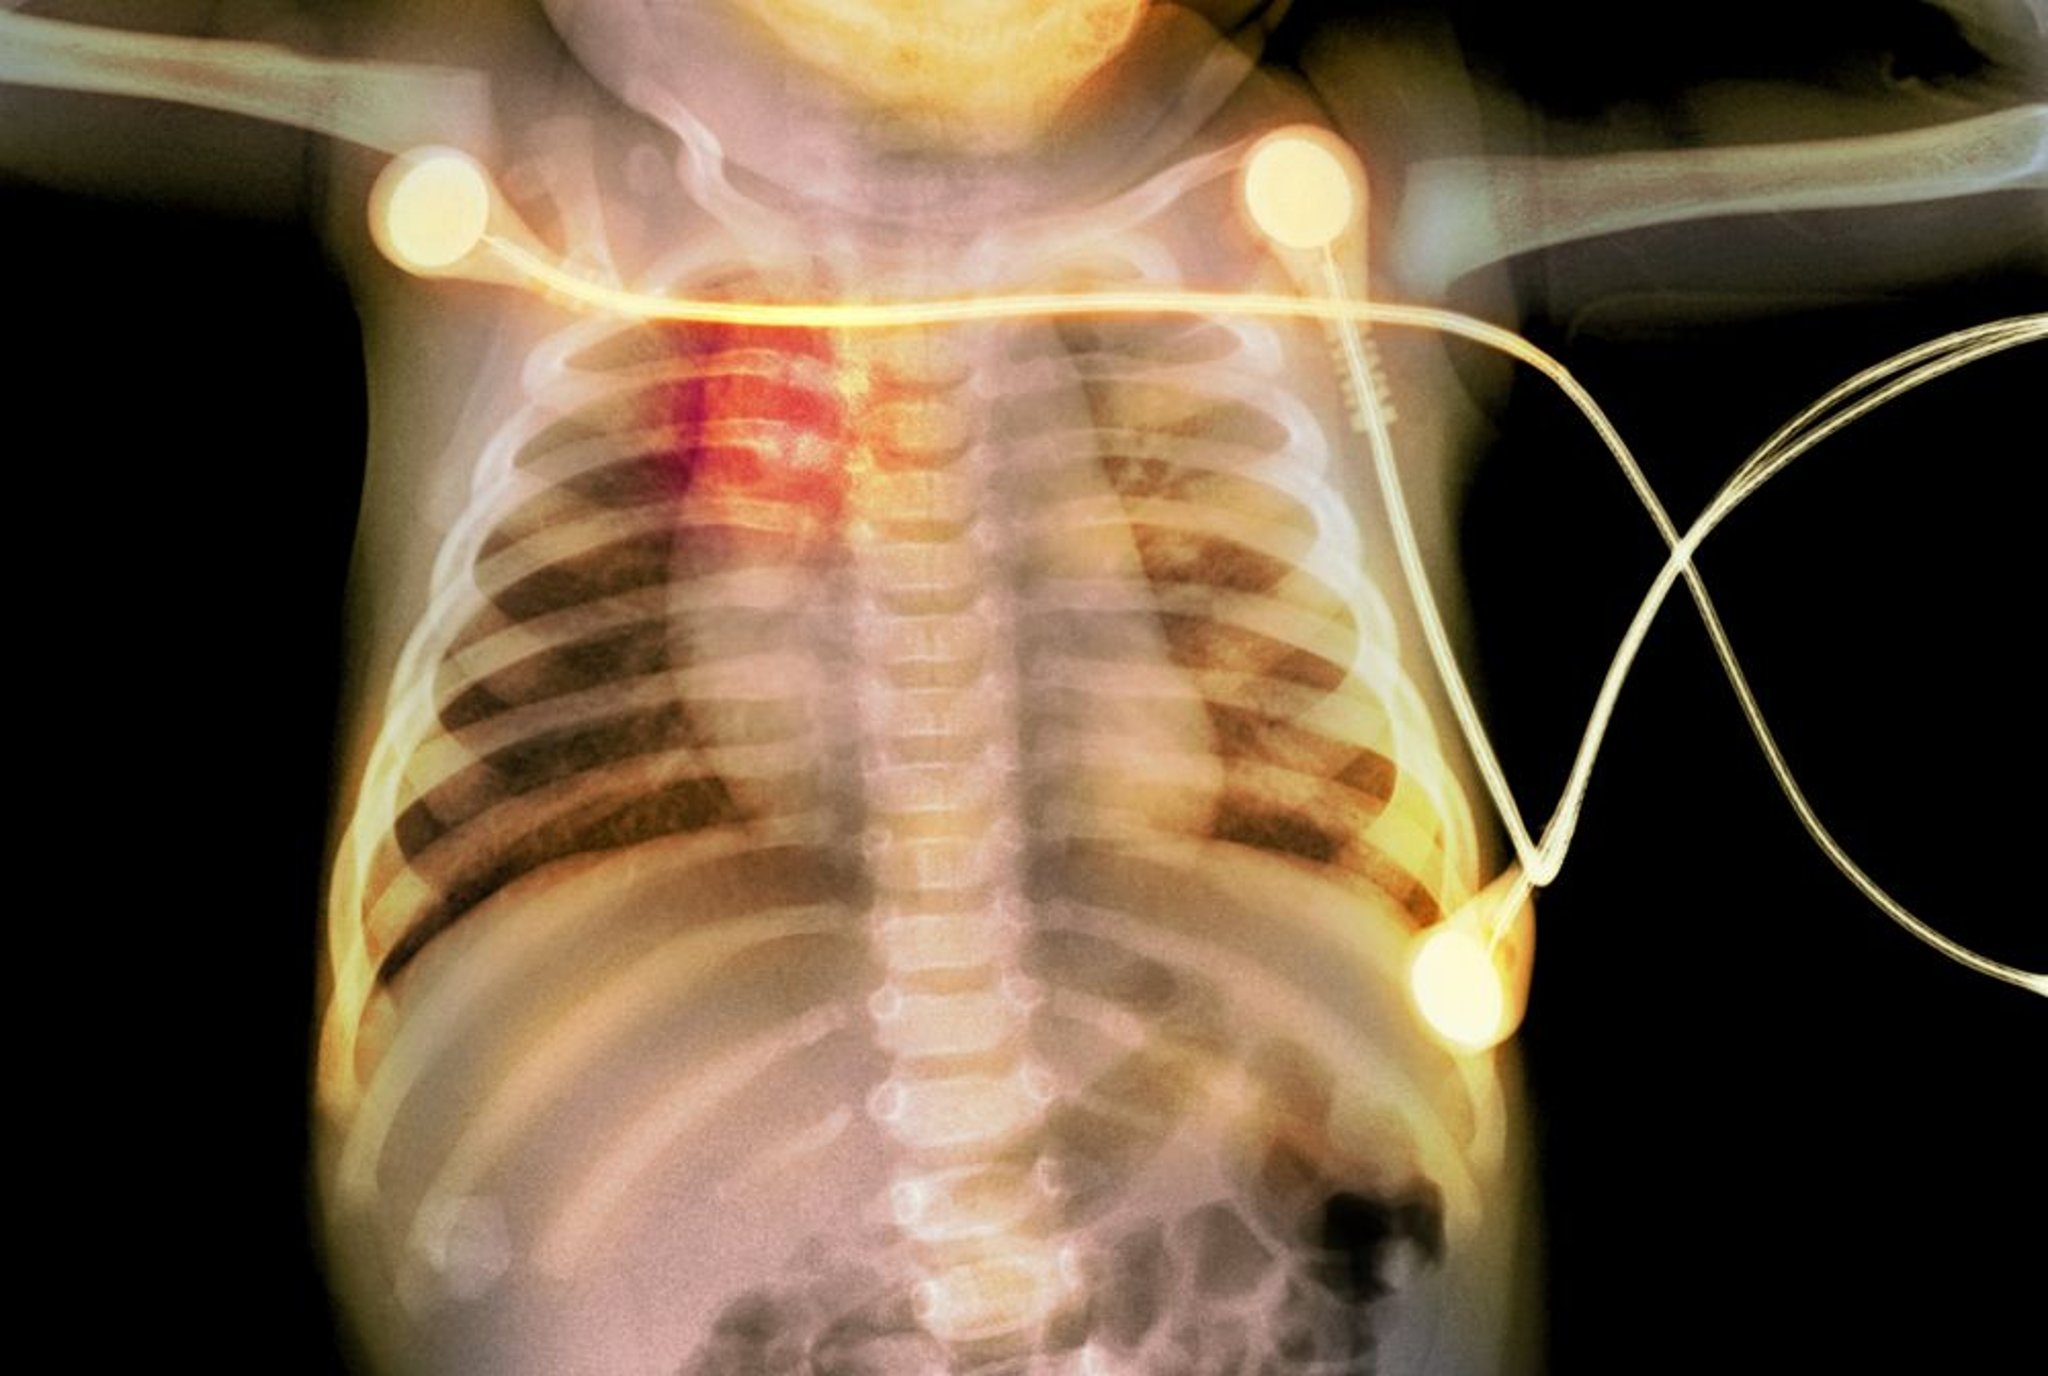

Rippenfrakturen bei einem Säugling

Diese Röntgenaufnahme zeigt Rippenfrakturen (rot hervorgehoben) bei einem Säugling, die auf Kindesmissbrauch hindeuten.

PHOTOSTOCK-ISRAEL/SCIENCE PHOTO LIBRARY